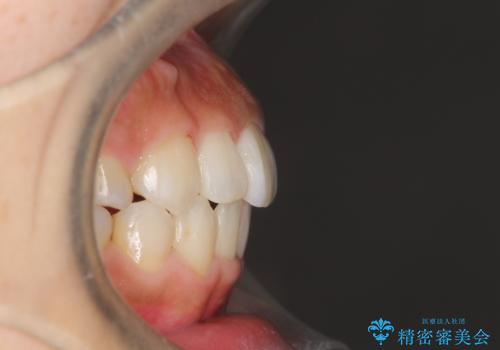

- 上顎の骨格性拡大+両側第1小臼歯抜歯 によりスペースを獲得、フルリンガルによるワイヤー矯正を計画した。

骨格的要因を背景にもつ不正咬合のため、歯列矯正単独での改善は困難と判断しましたが、患者さんとの相談の結果、歯列矯正単独で可能なところまで一緒に頑張りましょうということで、治療をすすめました。

シビアな叢生や開咬も改善することができ、想像以上の改善に時間をかけた甲斐があったと満足していただけました。